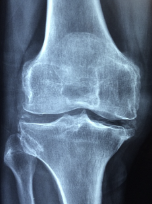

무릎 관절염 원인에 대해 알아보겠습니다. 무릎 관절염은 무릎 관절의 연골이 손상되거나 마모되어 통증, 염증, 운동장애 등을 일으키는 질환입니다. 무릎 관절염의 원인은 여러 가지가 있습니다. 가장 흔한 원인은 나이가 들면서 연골이 자연스럽게 마모되는 것입니다. 이를 퇴행성 관절염이라고 합니다. 퇴행성 관절염은 주로 50세 이상의 노인에게 많이 발생합니다. 다른 원인으로는 과체중, 스포츠나 직업상의 부상, 유전적 요인, 염증성 질환, 감염 등이 있습니다. 과체중은 무릎 관절에 과도한 압력을 가해 연골이 빨리 닳게 합니다. 스포츠나 직업상의 부상은 무릎 관절에 외부적인 충격을 주어 연골이 손상되거나 염증이 생기게 합니다. 유전적 요인은 무릎 관절의 구조나 연골의 품질에 영향을 줄 수 있습니다. 염증성 질환은 류마티스 관절염, 천식, 알레르기 등으로 인해 무릎 관절에 염증이 생기게 합니다. 감염은 바이러스나 세균 등이 무릎 관절에 침입하여 연골이 파괴되거나 염증이 일어나게 합니다.

- 3단계: 무릎에 부기가 생기고, 운동 범위가 줄어듭니다. 무릎에서 염발음이라고 하는 뚝뚝 거리는 소리가 들리며, 고관절에서도 소리가 날 수 있습니다. 연골이 사라지면서 관절 끝이 비정상적으로 마모되어 극심한 통증이 나타나며, 보행 장애가 생길 수 있습니다.

- 4단계: 연골이 완전히 없어지고, 뼈와 뼈가 직접 마찰합니다. 무릎이 붓고 커진 것 같고, 다리가 O자로 휘어집니다. 일주일에 4일 이상 잠을 설치게 하는 통증이 있으며, 평지에서도 절뚝거리며 걷습니다.